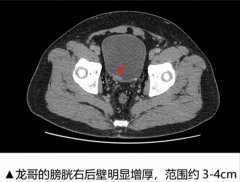

膀胱癌 龙哥 血尿 2026/02/13